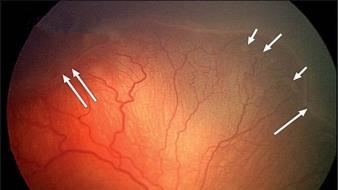

3.急性白血病的眼部表现

急性白血病的眼部直接浸润病变较为少见,更多见的是出血、血栓形成、贫血等带来的继发眼底改变。视网膜出血、棉绒斑是急性白血病累及眼底时的常见表现,也可出现眼底 Roth 斑。如图可见急性白血病眼底火焰状出血、棉绒斑和 Roth 斑同时存在。